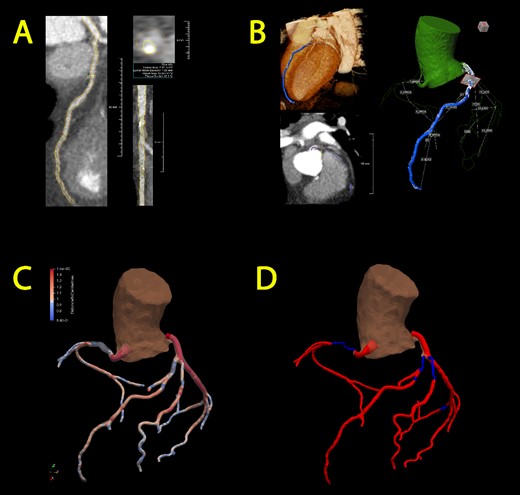

A custom AI-based algorithm was developed for semi-automated segmentation, which allows to create a patient-specific coronary artery model using computed tomography angiography (CTA) imaging. CTA data are imported into dedicated software QAngio CT Research Edition (v3.1.5.1 Medis Medical Imaging, Leiden, The Netherlands), where an initial segmentation of the coronary anatomy is generated. Subsequently, a manual review is conducted to refine the segmentation when necessary (Fig. 1A and B). Vessels with an outer diameter less than 1.5 mm are excluded from segmentation in consideration of their clinical irrelevance.

Semi-automated segmentation of the coronary artery tree, followed by manual refinement of each segmented artery (A) and transformation into a 3D representation (B). Subsequently, incorporation into an overall coronary artery structure follows through two models: the gradual flow model (C) and the stenosis detection model (D). Optimal blood flow is represented in red, while diminished blood flow is denoted by the color blue.

The model incorporates quantitative data pertaining to the lumen area, derived from measurements taken at varying distances from the open lumen wall to the centerline of the vessel at specific points. These data serve as a metric for assessing stenosis severity within the coronary artery model. Two distinct 3D models are constructed utilizing the acquired data; (1) a gradual flow model featuring a continuous representation of the lumen area variations (Fig. 1C) and (2) a stenosis detection model that identifies transition points where the area undergoes a 70% reduction or increase (Fig. 1D), thereby pinpointing the initiation and conclusion of significant stenotic vessel segments.